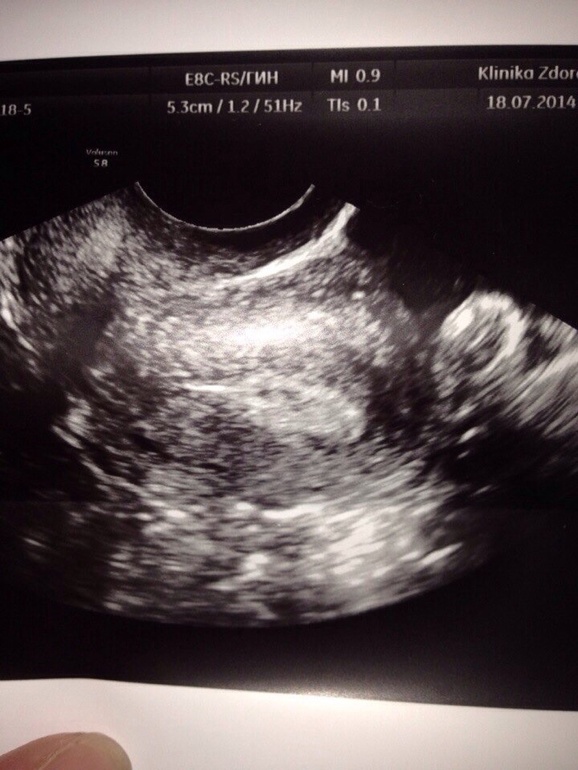

Девочки, как я уже писала я была на УЗИ, мне дали снимки и т.д. Приехали с мужем домой он такой дай посмотрю, и начинает разглядывать снимки и такой выдает Кать а это че? Я подхожу смотрю в полости матки какая-то черная точка, может это какие-то помехи конечно

, да к тому же я думаю врач то точно что то сказала б, посмотрите девочки пожалуйста, может я просто уже с ума схожу!?

Черная точка практически в центре? похожа на глазик у кролика(белое пятно в форме кролика))))))

там все в точках

ПЯ больше, его сразу видно, ни с чем не спутаешь ))))

ПЯ нету(((( оно сетсе намного! Такой пузыречек. А тут нету(